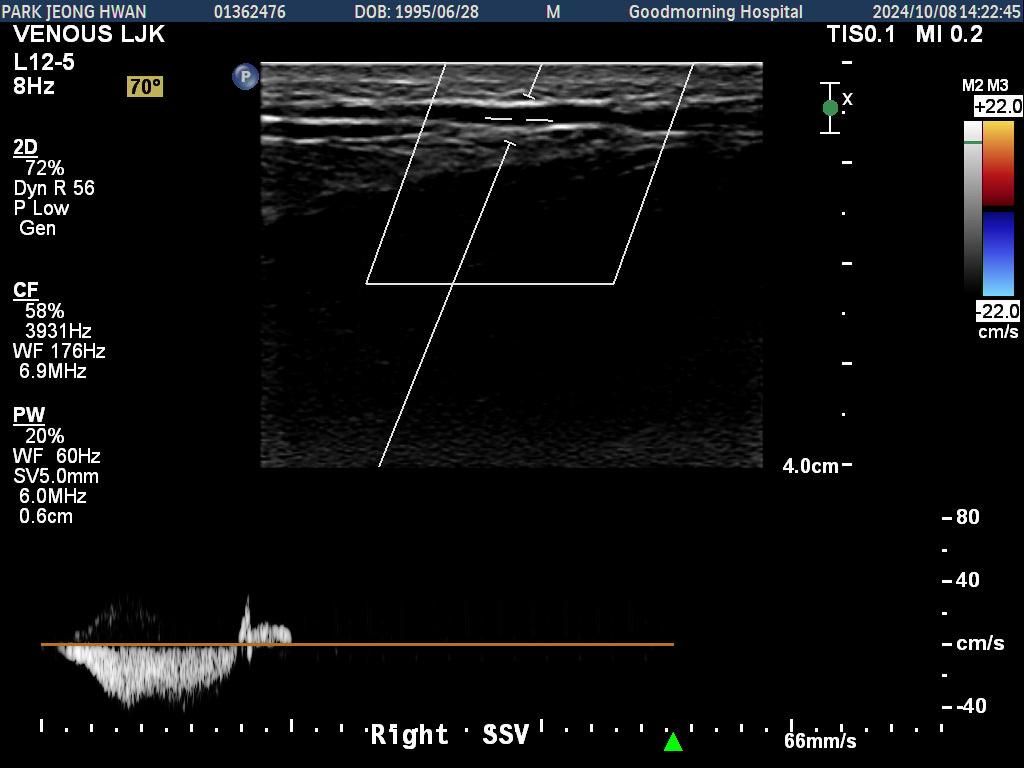

오른쪽 다리만 찍은 거구요. 종아리에서 사타구니까지 부분별로 찍었습니다.......................

• 1번 째 사진

• 2번 째 사진

• 3번 째 사진

• 4번 째 사진

• 5번 째 사진

• 6번 째 사진

• 7번 째 사진